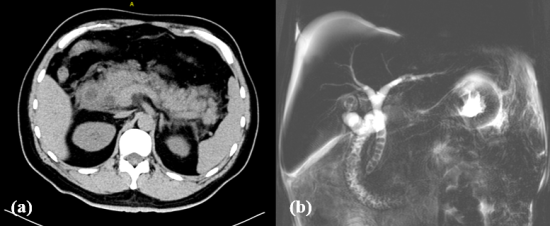

王刚主任了解病情后,结合患者临床表现、实验室检查及影像学检查结果,迅速给出了SAP的明确诊断,并立即采取“升阶梯”的经典治疗模式。因胆囊肿大明显,在彩超室会诊后,给予患者彩超引导下经皮经肝胆囊穿刺外引流的处置,同时开启了胆汁转流的辅助治疗。但MRCP结果令人触目惊心:患者的胆总管、肝总管及肝内胆管均扩张,且胆总管内满布结石呈“串珠样”,最大长径可达3cm,伴胆囊多发结石。

图 1a 胰腺CT示胰腺肿胀,边缘毛糙,伴一定量渗出,胆总管及十二指肠均扩张

图1b MRCP示胆总管、肝总管及肝内胆管均扩张,且胆总管内满布结石呈“串珠样”